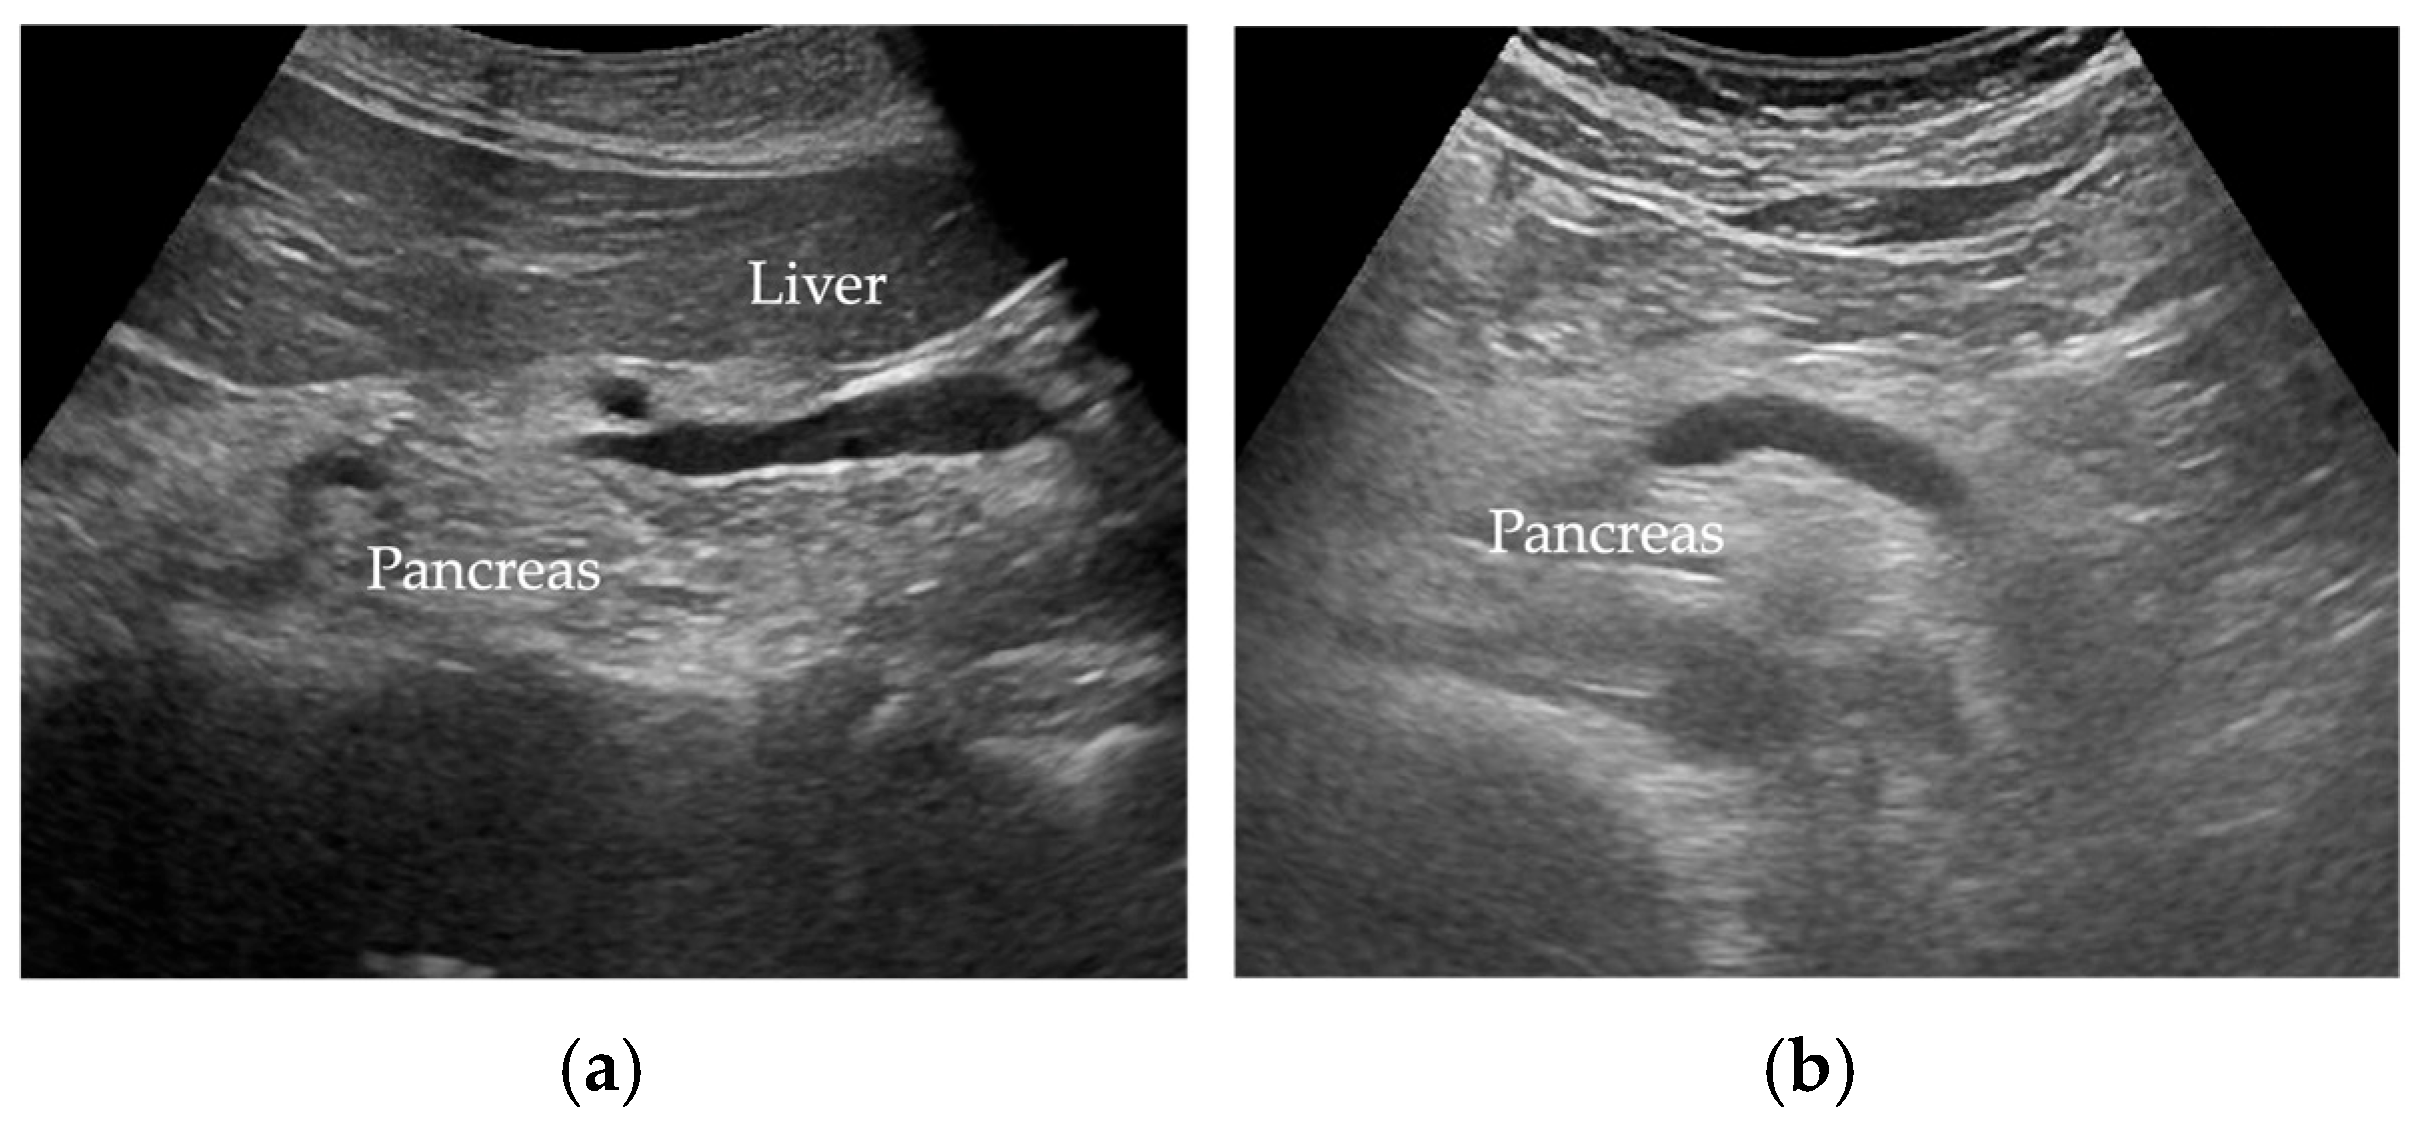

Wang et al. [35] reported FP was diagnosed when there was an increase in echogenicity of the pancreatic body over that of the kidney. Because the pancreas often could not be directly compared with the kidney within the same imaging window (Figure 2), the examiner assessed the differences between hepatic and renal echogenicity, and between hepatic and pancreatic echogenicity, to obtain an objective pancreatorenal echo contrast [35]. In another study, pancreatic echogenicity was compared to the liver echogenicity at the same depth on a longitudinal scan taken near the abdominal midline [36]. Figure 2 shows ultrasonographic images of a non-fatty pancreas and a fatty pancreas.

Figure 2.

Ultrasonographic images show (a) a non-fatty pancreas with normal echogenicity and (b) a fatty pancreas with increased echogenicity of the pancreatic body.